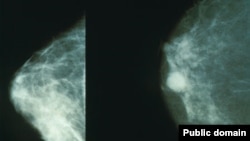

پستان سرطانی(راست)

دانشمندان می‌گویند موفق به شناسایی یک مولکول کلیدی در انتشار سرطان‌ پستان و ریه شده‌اند که از کار انداختن آن جلوی پیشرفت این بیماری به سایر نقاط بدن را می‌گیرد.